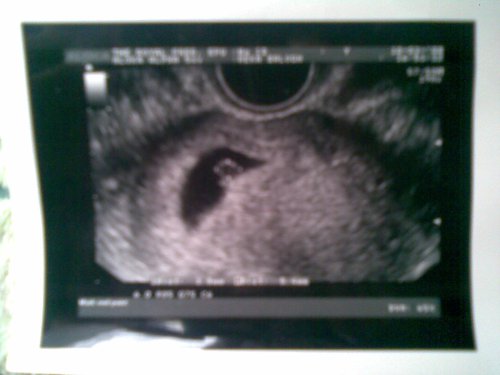

Nati és többiek! Csatolom a képet. De ilyet sajna ne várjatok - aki még szintén ezután megy - mert ezt nekem itt Londonban csinálták, és úgy tűnik, hogy ez nagyon jó minőségű Uh gép, mert a többiekét amit láttam, csak egy kis folt volt és kész. Ezen meg simán látszik a baba is. Bár maga a kép annyira itt nem lesz jó minőségű, mert a kapott papír képet mobillal fotóztam le. De azért hátha otthon is vmelyik dokinak van egy komolyabb Uh-ja!

Az első kép a babánkról!

mindössze 3mm-es és ekkor volt cca 5 hetes.

Nagyon szép a babyd! :) De honnan a lópikulából tudjátok, hogy fiú lesz? Mondjuk a méretek alapján én is arra gondolok. 5 hetesen 3mm... De várj, ez nem esetleg a petezsák mérete? Mert nekem 6+2-n volt maga a baby 3.2mm és ahogy nézegettem, ez teljesen átlagos méret. Azért remélem ő pedig kiscsaj. :)